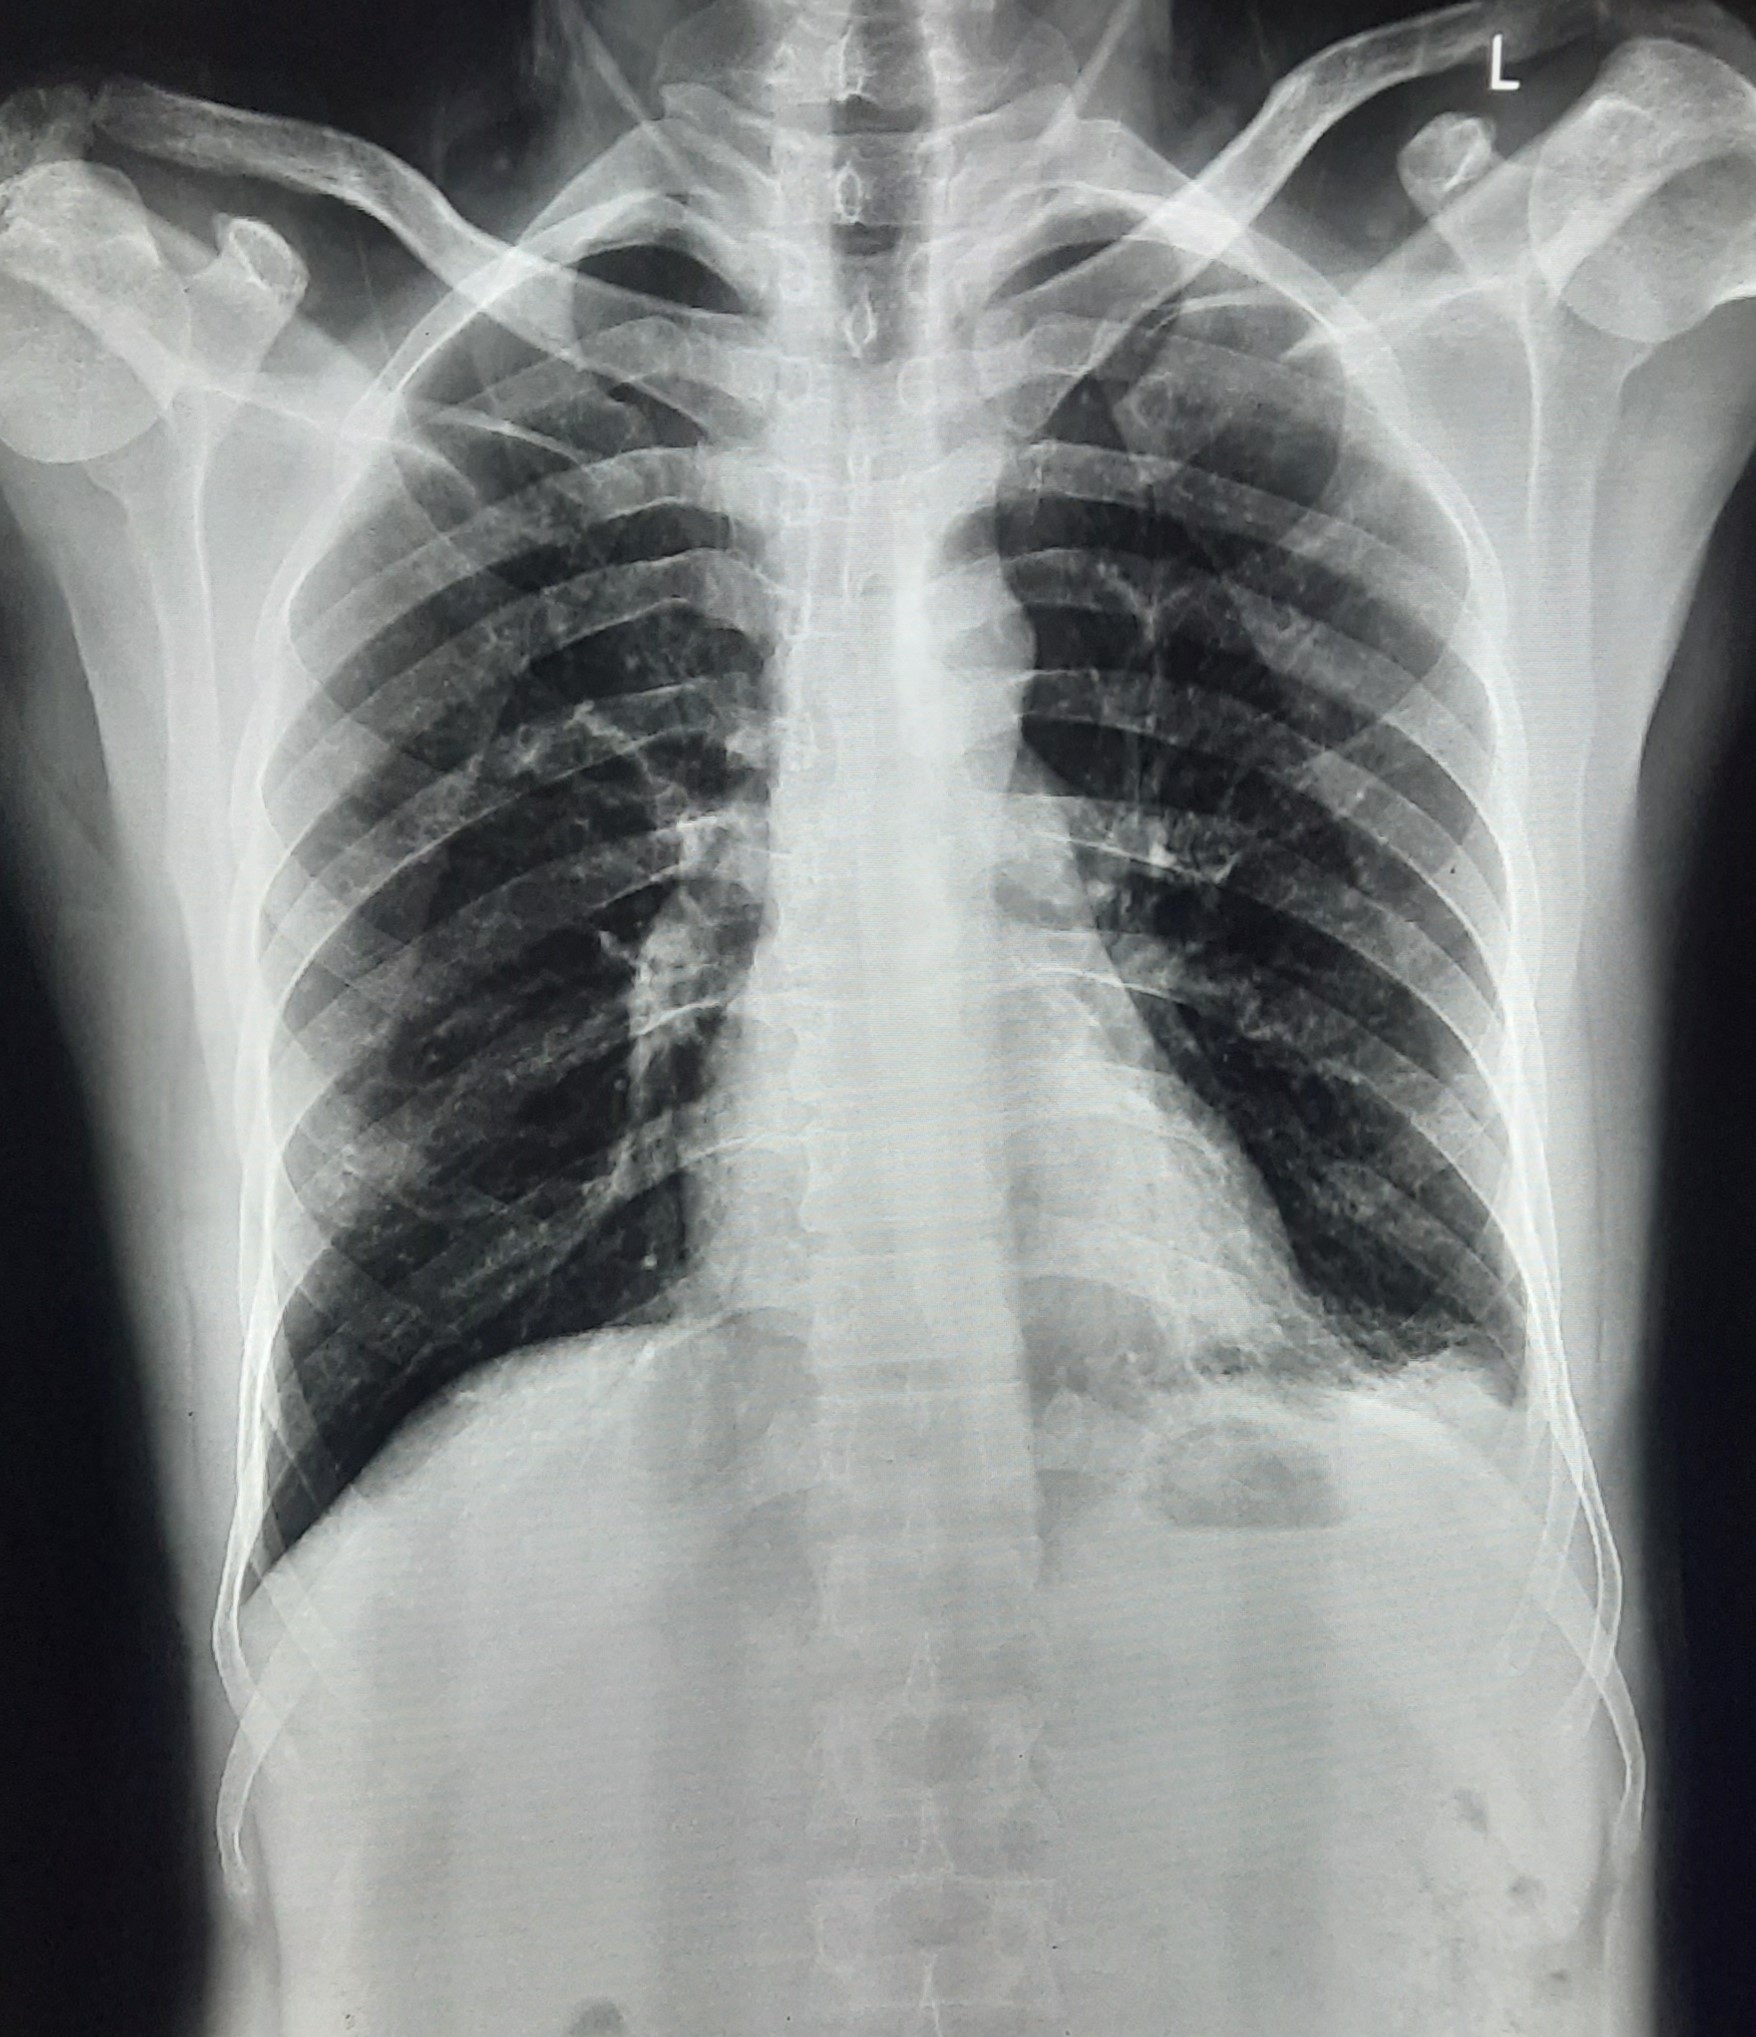

| 51 | IGGMC, Nagpur, Nagpur | P2 | 29-4421 | Santosh Neware | Consent taken on Paper | 40 Yrs. |

Provisional Diag : Pulmonary Tuberculosis

Final Diag : Pulmonary tuberculosis (Microbiologically Confirmed PTB) |

TB Case (Confirmed) | Right Upper & mid zone fibro cavitary lesion present, upward pull of right hemidiaphragm, tracheal pull right sided | Abnormality visible on x-ray |